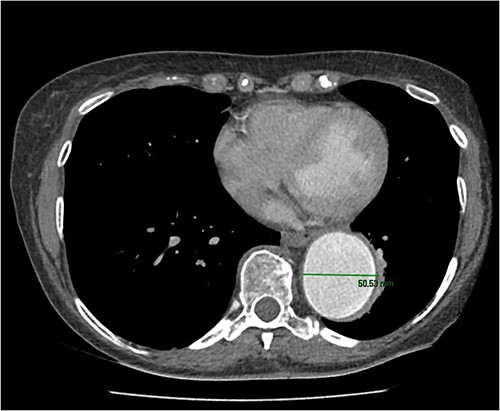

An 8 mm Gelweave graft was anastomosed to the left subclavian artery. Standard cannulation technique was used with the distal aorta and the right atrium. The distal aorta was sized and a 30/32 mm (15 cm length) Thoraflex graft was anastomosed with 4–0 prolene and reinforced with 1.5 cm Teflon. The supra-aortic vessels were reimplanted separately; deep hypothermia (20°C) was utilized for neuroprotection with antegrade cerebral perfusion and near infrared spectroscopy monitoring. Proximal aorta anastomosis followed patient rewarming. Her post-op CT aorta showed adequate perfusion and FET placement. A 3D reconstruction is shown in Figs 2 and 3. She was discharged on Day 10 and successful TEVAR was undertaken 8 months later (Fig. 4). Follow-up 24 months later showed no evidence of endoleak, stent migration or fracture.

3D reconstructed CT thoracic aorta image showing successful FET implantation and TEVAR.